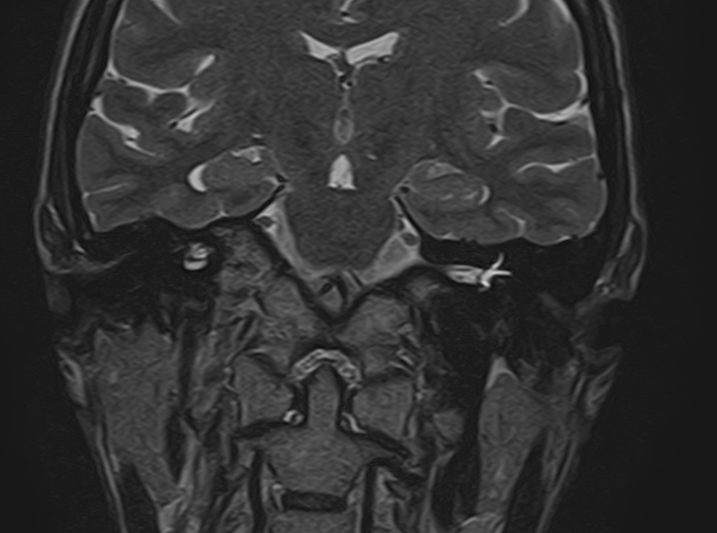

Внутреннее ухо – важная часть слуховой и вестибулярной систем тела человека, находящаяся в толще пирамиды височной кости.

Внутреннее ухо содержит слуховой орган (улитку) и орган равновесия (преддверие и полукружные каналы), патологические изменения которых в свою очередь приводят к развитию нейросенсорной тугоухости и вестибулярных нарушений.

Во время исследования пациент лежит на столе томографа неподвижно около 30 минут, на область исследования устанавливается специальная головная катушка для получения четких изображений.